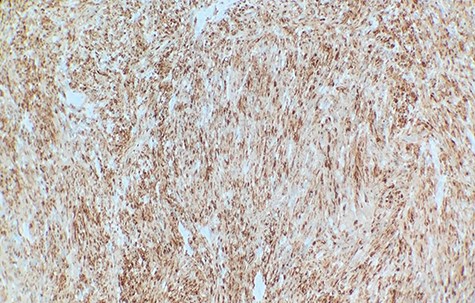

Macroscopically, the tumor appeared encapsulated, rubbery and pink-tan in color. Microscopic examination reveals that tumor composed of biphasic spindle hypercellular Antoni A areas and hypocellular Antoni B areas (Fig. 1). Higher magnification reveals that spindle tumor cells are narrow, elongate, wavy with tapered ends interspersed with collagen fibers (Fig. 2). Immunohistochemical staining revealed that most tumor cells reacted strongly for S-100 protein (Fig. 3). Combined with immunohistochemical profile, these histological features are diagnostic of benign schwannoma. Patient was discharged home on the same day as the operation. At the 1-month follow-up, he was symptom free, without any pain or sensory disturbances.

Immunohistochemical staining revealed that tumor cells are strongly positive for S-100 protein (×40).